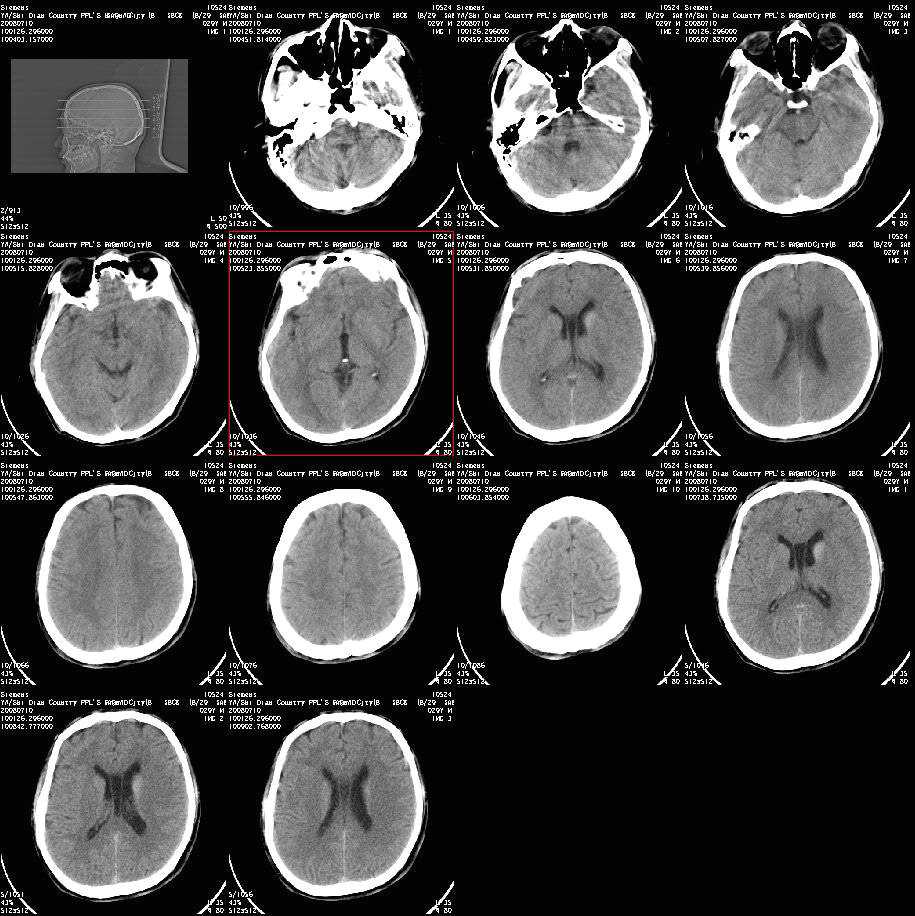

以下是引用随光逐影在2008-7-10 15:19:00的发言:[br]1)考虑左侧尾状核钙化。2)透间隔间腔与vergae腔并存。

以下是引用卜一在2008-7-10 16:43:00的发言:[br]1)考虑左侧尾状核钙化。2)透间隔间腔形成。支持!